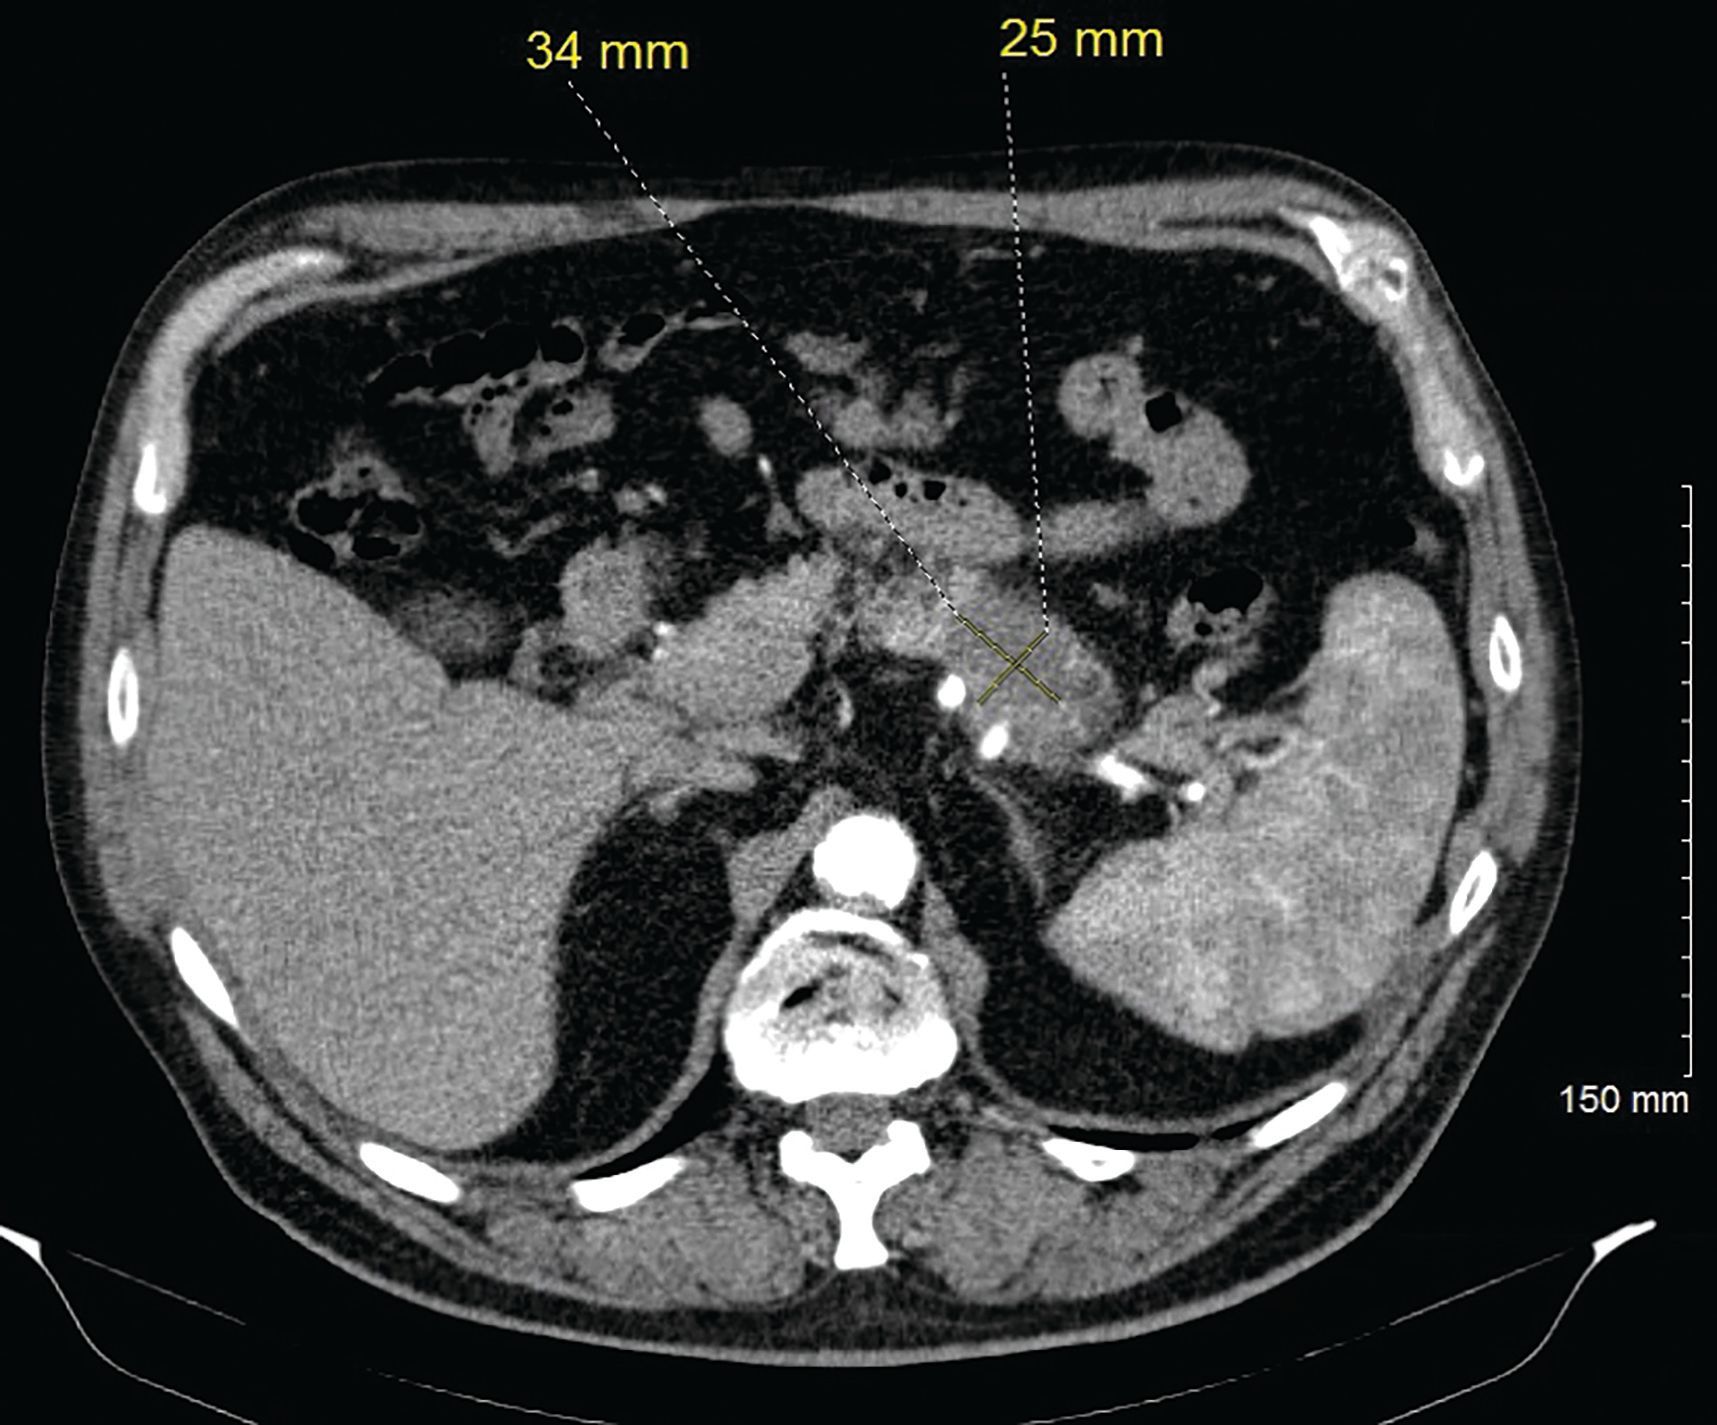

Figure 2. Axial contrast enhanced CT (arterial phase) demonstrates pancreatic tail lesion with relative hypoenhancement, corresponding to the focus of uptake on the recent positron emission tomography (PET) imaging. There was dilatation of the pancreatic duct distal to this finding (not shown), which did not show fluorodeoxyglucose (FDG) uptake on PET.

A Caucasian male, aged 74 years, was incidentally found to have a pancreatic mass during a surveillance imaging positron emission tomography (PET) scan for his prior malignant melanoma. The PET scan detected a suspicious uptake in the pancreatic tail corresponding to a subtle 2.6 cm x 1.8 cm region of low attenuation with a standardized uptake value of 7.5 (Figure 1). A CT scan of the abdomen revealed this to be a hypodense mass in the distal body/tail portion of the pancreas measuring 3.4 cm x 2.5 cm (Figure 2). Further work-up with upper endoscopy and endoscopic ultrasound biopsy revealed invasive PDAC. Family history was significant; his father and paternal grandfather had both received a diagnosis of PDAC around age 70 years and died from it. A genetic counseling visit and germline multigene hereditary pancreatic cancer panel testing detected no pathogenic sequence variants or deletions/duplications in the analyzed genes; these included APC, ATM, BRCA1, BRCA2, CDKN2A, MLH1, MSH2, MSH6, PALB2, PMS2, STK11, and TP53 (sequencing and deletion/duplication), and EPCAM (deletion/duplication only).